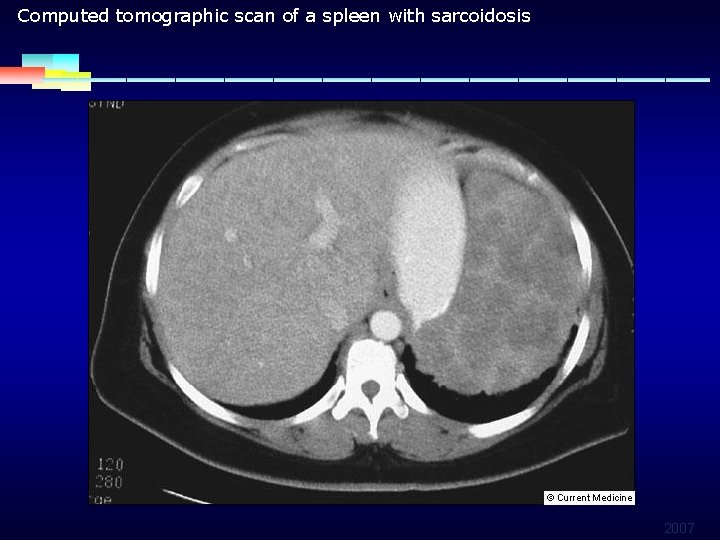

Computed tomographic scan of a spleen with sarcoidosis 2007